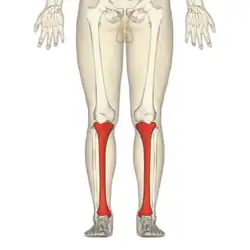

The photographs and radiographs illustrate the application and emplacement of an external fixator, an Ilizarov apparatus, to repair the open fracture of the lower left leg of a man. The photographs were taken four weeks after the patient fractured the shinbone (tibia) and the calfbone (fibula) of his left leg, and two weeks after the surgical emplacement of the Ilizarov apparatus to immobilise the leg and isolate the wound and fracture site to facilitate healing.

X-ray of the open fracture of the left leg; the external fixator was installed ca. 24 hrs. in hospital.

X-ray of the open fracture of the left leg; the external fixator was installed ca. 24 hrs. in hospital. X-ray of the open fracture site immediately after installation of the Ilizarov apparatus.